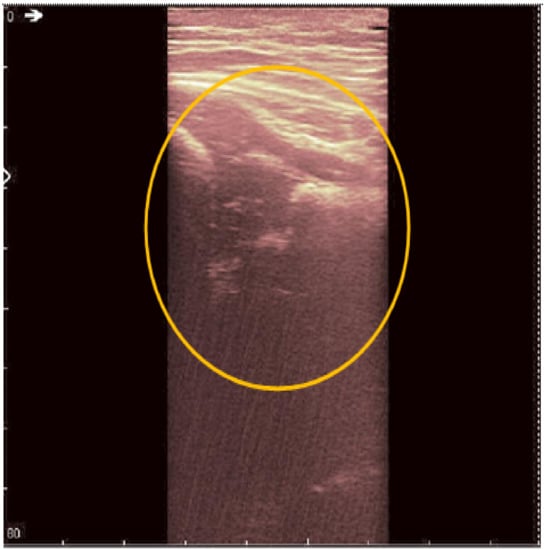

The original recording is displayed in Figure 3. As a first processing step, a color palette has been added to the original ultrasound in order to better highlight the noise and noise-free zones (Figure 4). The wavelet-based filter, as described in Section 2, is applied, and the processed image is shown in Figure 5.

We can remark, when analyzing the zoomed parts of Figure 4 and Figure 5 (the acetabulum), that in the original image speckle noise appears, strongly affecting the image. The filtering system proposed in this paper does not completely remove the speckle but brightens the image, at the same time not oversmoothing the original image. The main bone structure can be better outlined. A comparison between the same zoomed region of interest in the original image and denoising result, showing the disappearance of the speckle grains (Figure 6)—resulting thus in a smoother image where anatomical features can be better outlined.

Figure 4. Original data with an added color palette. A region of interest containing some speckle grains was encircled in yellow.

Jpm 12 01328 g004